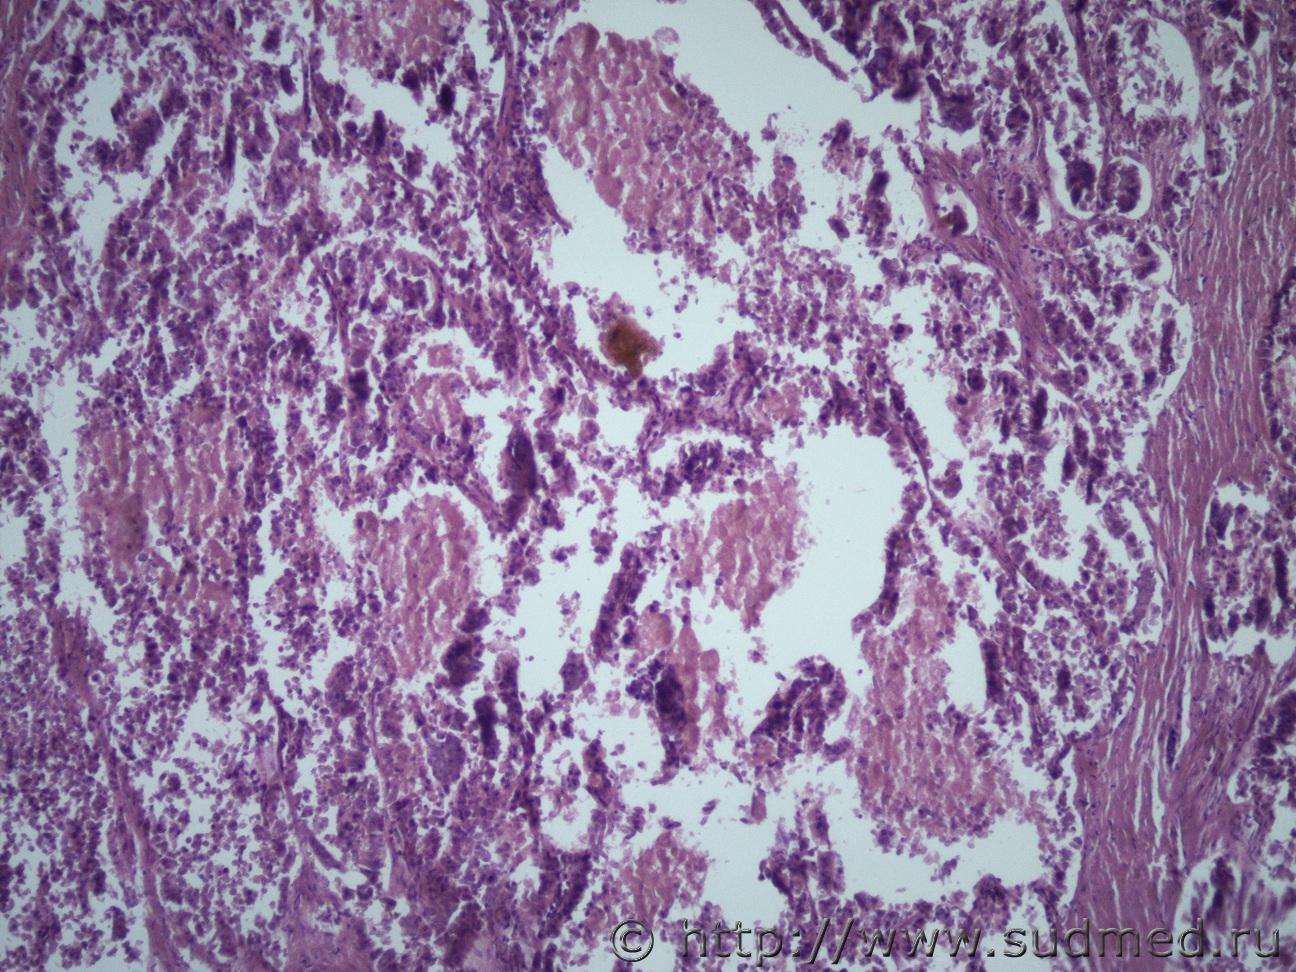

опухоль печени |

IVANNES опухоль печени 21.11.2018 - 10:39

Anton Эпителий желчного типа, д.б. холангиокарцинома. 21.11.2018 - 14:02

andy_bob Железистая ткань с фигурами патологического митоза... 29.11.2018 - 12:39![]() ![]() |